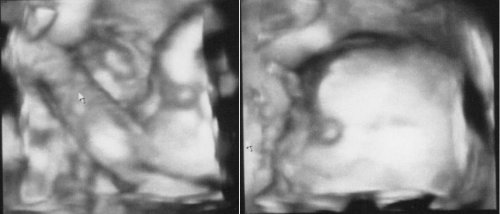

Naše twins 🙂 výbavička